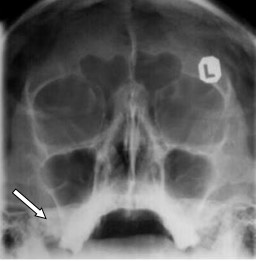

Na radiogramie czaszki strzałką zaznaczono

A. zachyłek jarzmowy.

B. część skalistą kości skroniowej.

C. gałąź żuchwy.

D. zatokę szczękową.